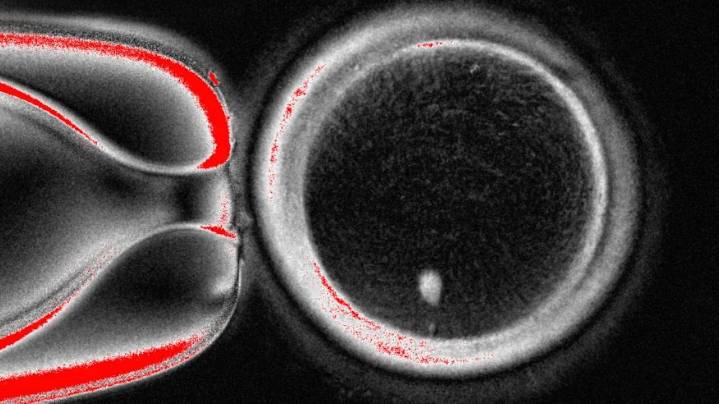

The OHSU team removed the nucleus from a human egg cell and replaced it with the nucleus from a human skin cell. But a skin cell contains two sets of chromosomes